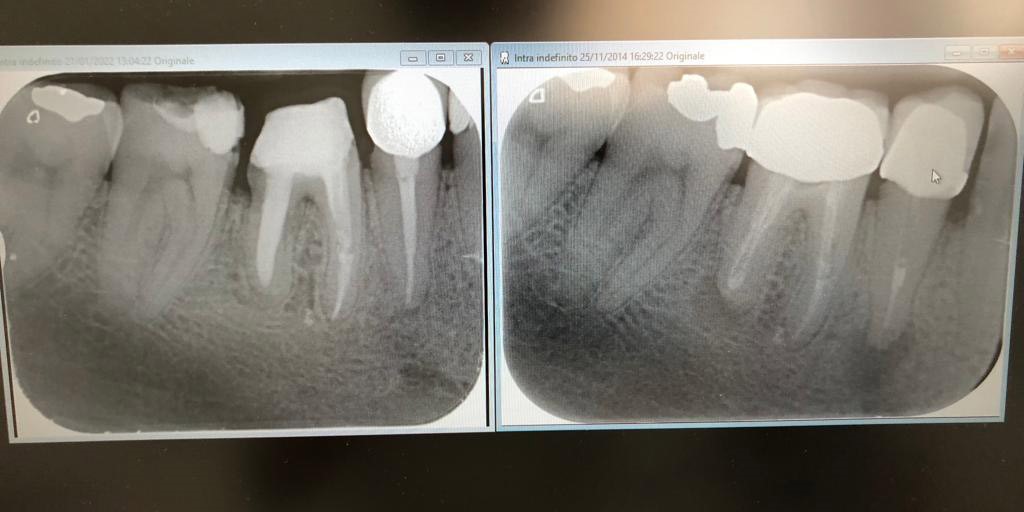

Nell'immagine precendete possiamo vedere a destra denti devitalizzati in modo non corretto, presenza di infezioni apicali, mentre su quella di sinistra ritrattamento endodontico e scomparsa delle infezioni a 8 mesi.